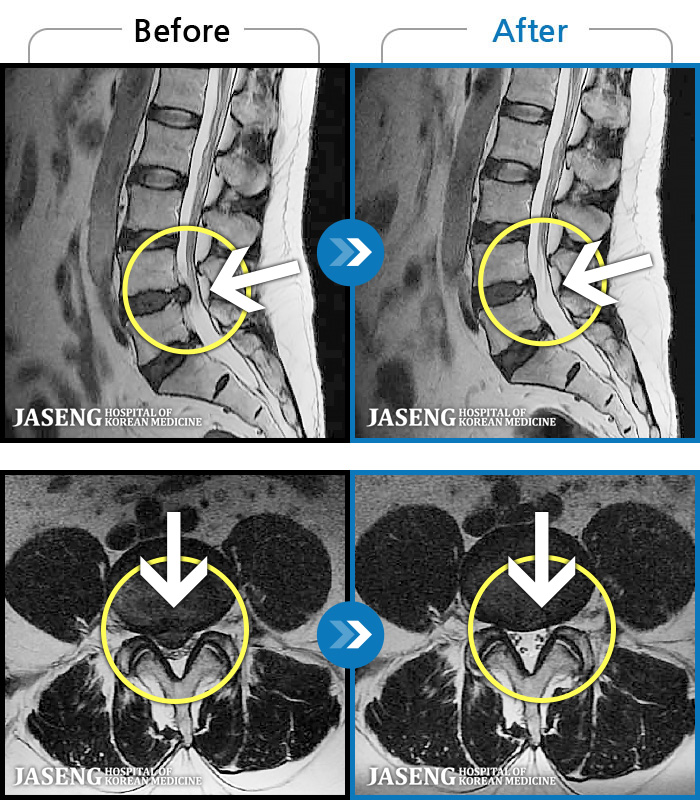

MRI ġ

119 MRI ũ ʸ Ȯϼ.

㸮 ؼ ̱ ư ϴ.

[Կñ:24.01.30~24.07.09]

[_㸮ũ] ٸ ؼ ɾٴϱ

No.119

ȸ 560

2024.12.24